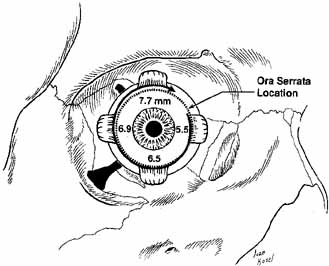

called the spiral of Tillaux (see Fig. 15). The medial rectus inserts nearest at 5.5 mm posterior to the limbus, and

the superior rectus inserts farthest from the limbus at 7.7 mm. The

relationship of the muscle insertions and the ora serrata is clinically

important. A misdirected bridle suture passed through the insertion

of the superior rectus muscle could perforate the retina. The

posterior third with the anterior two-thirds (see Fig. 19).  Fig. 15 Anterior view of the right globe. The spiral of Tillaux is shown with superimposed

location of the ora serrata. Fig. 15 Anterior view of the right globe. The spiral of Tillaux is shown with superimposed

location of the ora serrata.